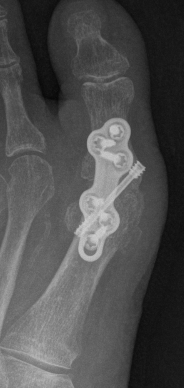

Arthrodesis

Indications

- hallux valgus with arthritis

- severe hallux valgus

- neuromuscular disease i.e. cerebral palsy

- rheumatoid arthritis

- salvage procedure for failed procedures

Technique

Approach

- dorsal approach

- medial approach

Position

- 10 - 15° valgus

- 10- 15° dorsiflexion relative to plantar surface / 20 - 25° relative to metatarsal shaft

Fixation

- screws / plate / screws + plate